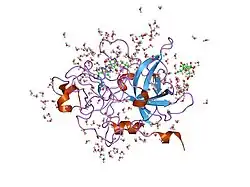

Structure

Urokinase is a 411-residue protein, consisting of three domains: the serine protease domain (consisting of residues 159–411), the kringle domain (consisting of residues 50-131), and the EGF-like domain (consisting of residues 1-49). The kringle domain and the serine protease domain are connected by an interdomain linker or connecting peptide (consisting of residues 132–158). Urokinase is synthesized as a zymogen form (prourokinase or single-chain urokinase), and is activated by proteolytic cleavage between Lys158 and Ile159. The two resulting chains are kept together by a disulfide bond between Cys148 and Cys279.[9]